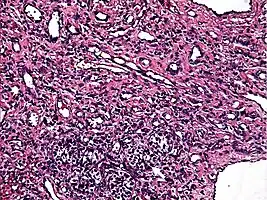

| Micrograph of a kaposiform hemangioendothelioma with "glomeruloid" nodules of endothelial cells. | |

- Kaposiform hemangioendothelioma (also known as "Infantile kaposiform hemangioendothelioma"[4]) is an uncommon vascular tumor, first described by Niedt, Greco, et al. (Hemangioma with Kaposi's sarcoma-like features: report of two cases.(Niedt GW, Greco MA, Wieczorek R, Blanc WA, Knowles DM 2nd. that affects infants and young children, with rare cases having also been reported in adults. Pediatr Pathol. 1989;9(5):567-75.)[3]: 596 [4]: 1782